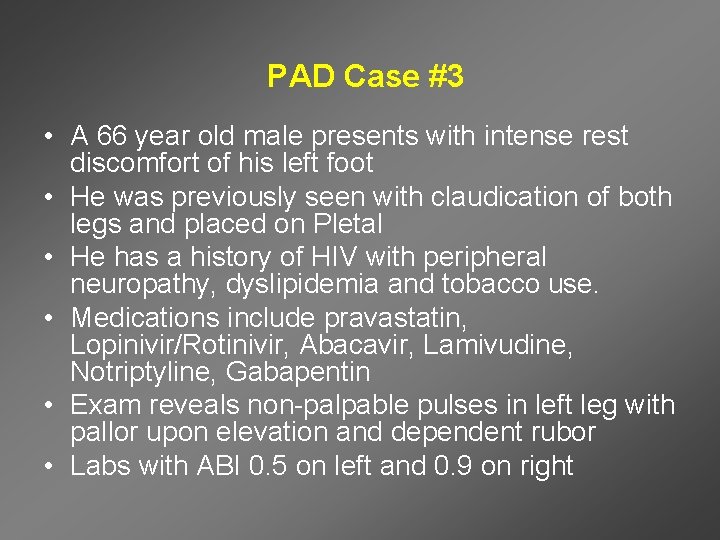

PAD Case #3 • A 66 year old male presents with intense rest discomfort of his left foot • He was previously seen with claudication of both legs and placed on Pletal • He has a history of HIV with peripheral neuropathy, dyslipidemia and tobacco use. • Medications include pravastatin, Lopinivir/Rotinivir, Abacavir, Lamivudine, Notriptyline, Gabapentin • Exam reveals non-palpable pulses in left leg with pallor upon elevation and dependent rubor • Labs with ABI 0. 5 on left and 0. 9 on right